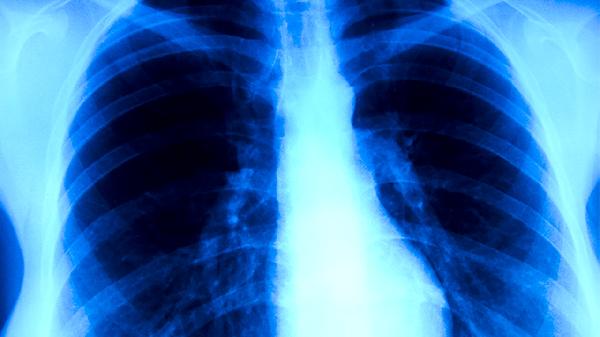

耐药性肺结核患者应严格隔离治疗,居住环境保持通风干燥。饮食上保证每日优质蛋白摄入量不低于1.5g/kg体重,多吃鸡蛋、鱼肉等易消化食物。注意监测肝肾功能,避免使用损害肝肾的药物。所有密切接触者都需进行结核菌素试验筛查。治疗期间每2个月复查痰菌和胸部CT,全程治疗通常需要18-24个月。出现任何症状加重都应及时复诊,切勿自行调整用药方案。